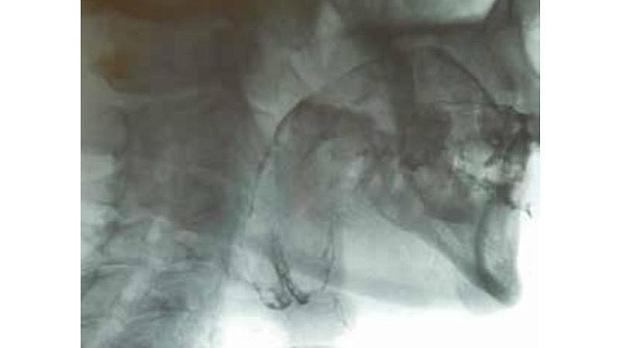

Статьи: Фиброваскулярный полип пищевода.

Авторы: А.В. МИХЕЕВ, С.Н. ТРУШИН, Е.К. 1 СУРОВ, С.В. СНЕГУР 2

Об авторах: 1. ГБОУ ВПО «Рязанский государственный медицинский университет им. И.П. Павлова»

2. ГБУ Рязанской области «Областная клиническая больница»